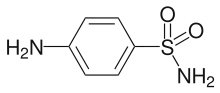

Sulfonic acids have functionality R−S(=O)2−OH.[20] They are strong acids that are typically soluble in organic solvents. Sulfonic acids like trifluoromethanesulfonic acid is a frequently used reagent in organic chemistry. Sulfinic acids have functionality R−S(O)−OH while sulfenic acids have functionality R−S−OH. In the series sulfonic—sulfinic—sulfenic acids, both the acid strength and stability diminish in that order.[21][22] Sulfonamides, sulfinamides and sulfenamides, with formulas R−SO2NR′2, R−S(O)NR′2, and R−SNR′2, respectively, each have a rich chemistry. For example, sulfa drugs are sulfonamides derived from aromatic sulfonation. Chiral sulfinamides are used in asymmetric synthesis, while sulfenamides are used extensively in the vulcanization process to assist cross-linking. Thiocyanates, R−S−CN, are related to sulfenyl halides and esters in terms of reactivity.